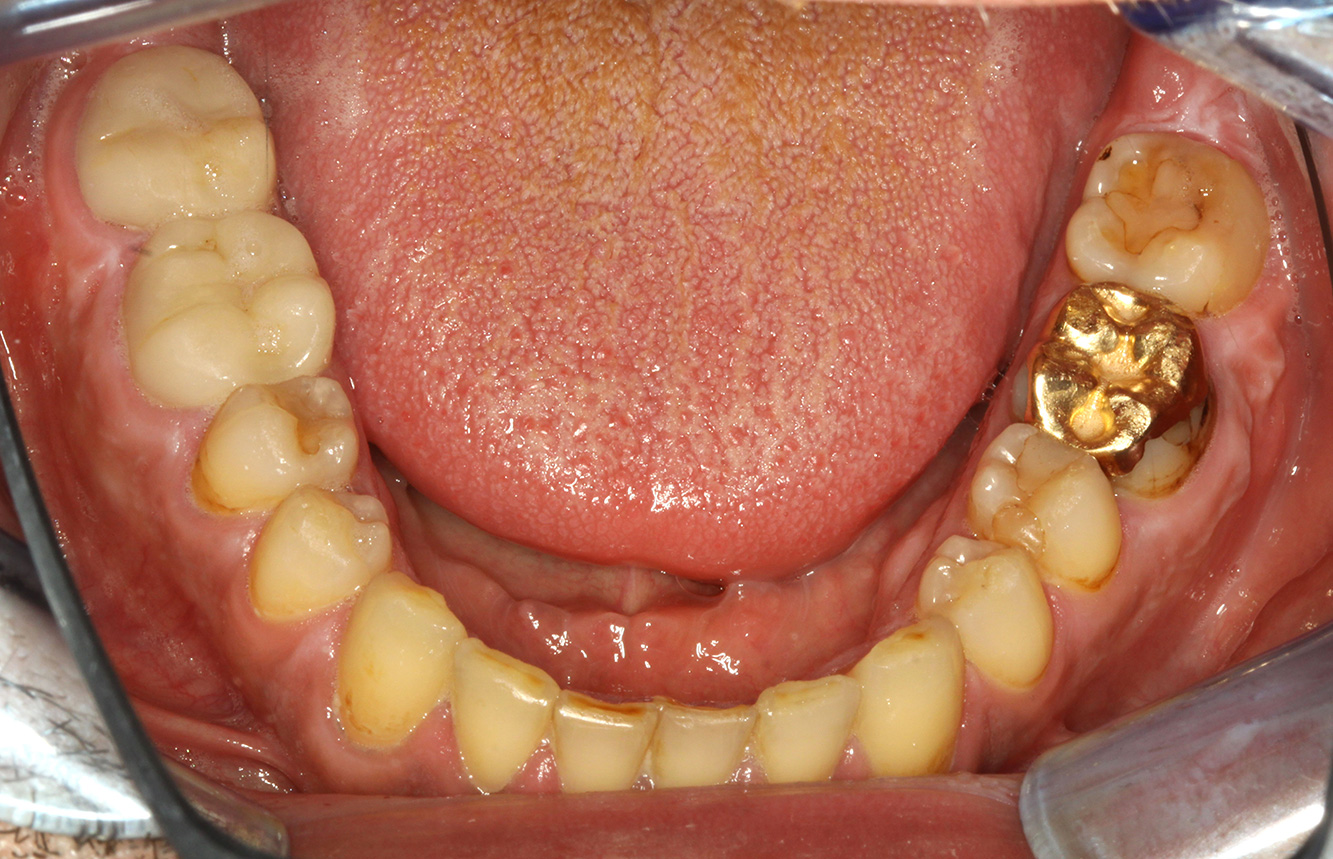

Patientenfälle nach IPCUm das Zusammenspiel der für den IPC definierten Bedarfs- und Risikofaktoren sowie die Auswirkungen einzelner Faktoren zu illustrieren, dienen nachstehende Fallbeispiele*. Die mundgesunde DiabetikerinEine 51-jährige mundgesunde Diabetikerin stellt sich zur Präventionssitzung vor. Die Blutzuckerwerte sind stabil bei einem HbA1c = 6,2%, folglich gilt sie mit dem entsprechenden Medikament Metformin (Antidiabetikum) als suffizient eingestellt. Die Patientin hat keine bestehenden Versorgungen oder orale Vorerkrankungen. Anhand der aktuellen Befunde lässt sich eine Gingivitis bei sonst stabilem parodontalem Zustand (Stage II, Grad B) feststellen. mehr Infos Fallpräsentation: Management komplexer ZahnprothetikEs ist längst bekannt, dass Mundgesundheit und Allgemeingesundheit in direktem Zusammenhang stehen und einen zum Teil bidirektionalen Einfluss aufeinander haben. Die Berücksichtigung beider Faktoren sind bei der Planung der oralen Prävention und Therapie der Patienten in der Zahnarztpraxis unabdingbar. Dabei ist oberstes Ziel, die Gesundheit und die Lebensqualität der Patienten sowohl aus zahnmedizinischer -und medizinischer Sicht zu erhalten. mehr Infos Der (mund)-gesunde Patient mit ImplantatenDer 55-jährige Patient gibt in der Anamnese an, keine Allgemeinerkrankungen zu haben und keine Medikamente einzunehmen. Die Lebensgewohnheiten des Patienten sind ebenfalls unauffällig. Der Patient hat einige zahnärztliche Restaurationen und zwei Implantate (2. und 4. Quadrant). Anhand der aktuellen Befunde lässt sich eine Gingivitis bei stabilem parodontalen Zustand am reduzierten Parodont (Stadium III, Grad A) feststellen. mehr Infos Der gesunde Patient mit parodontaler Vorerkrankung & PeriimplantitisEin 52-jähriger Patient stellt sich zur Präventionssitzung vor. Der Patient hat keine Allgemeinerkrankungen und nimmt keine Medikamente ein. Er hat verschiedene zahnärztliche Versorgungen und zudem zwei aktive kariöse Läsionen. Außerdem verfügt der Patient über vier Implantate (2., 3. und 4. Quadrant). Es zeigt sich eine parodontale Vorerkrankung (Stadium IV, Grad B). Derzeit herrschen stabile parodontale Verhältnisse, lediglich am Implantat regio 36 zeigen sich Sondierungstiefen (ST) von 5 mm. Zudem lässt sich eine Gingivitis feststellen. mehr Infos Der Diabetiker mit ParodontitisDieser Fallbericht eines 52-jährigen Mannes mit Typ-2-Diabetes und Parodontitis hebt hervor, wie durch individuelle Vorsorgemaßnahmen, die Gesundheit des Zahnhalteapparates erhalten bzw. das Fortschreiten der Erkrankung kontrolliert werden kann. mehr Infos Der 28-jährige Raucher mit ZahnerosionenDieser Fallbericht eines 28-jährigen Rauchers mit Zahnerosionen zeigt die Bedeutung personalisierter Patientenprofile. Er unterstreicht die Notwendigkeit, sowohl die Mundgesundheit als auch die allgemeine Gesundheit zu berücksichtigen, um Erkrankungen der Zähne bzw. des Zahnhalteapparates effektiv zu verhindern. mehr Infos Der Endokarditis-Patient mit aktiven KariesläsionenDer Patient ist 39 Jahre mit Z.n. Herzklappenersatz wegen Klappenfehlers und Endokarditis. Als Antikoagulans (Gerinnungshemmer) wird regelmäßig ASS 100 eingenommen. Aus dem Bereich Lebensstil ist die Ernährungsweise als kariesfördernd einzustufen, da mit hoher Regelmäßigkeit zuckerhaltige Lebensmittel sowie sechs bis sieben Mahlzeiten täglich verzehrt werden. Die Mundgesundheit des Patienten zeigt ein mittleres Kariesrisiko mit aktiven Läsionen. Das Parodontitisrisiko ist niedrig, es besteht eine Gingivitis. Es ergeben sich folgende Empfehlungen für die Prophylaxebehandlung. mehr Infos Die gesunde Patientin mit parodontaler VorerkrankungDie 68-jährige Patientin hat keine zahnmedizinisch relevanten allgemeingesundheitlichen Vorerkrankungen oder Medikation, auch aus dem Lebensstil ergibt sich kein besonderes Risiko. Die Patientin hat zwei Implantate (3. Quadrant, seit fünf Jahren) sowie eine parodontale Vorerkrankung (Parodontitis Stadium IV, Grad B) mit Zahnverlust. Derzeit zeigen sich stabile parodontale Verhältnisse. Für die Prophylaxesitzung ergeben sich vier Empfehlungen in den Bereichen Anamnese/Befund, Motivation/Instruktion, der Wahl der geeigneten Instrumente und für Resümee/Folgetermin. mehr Infos